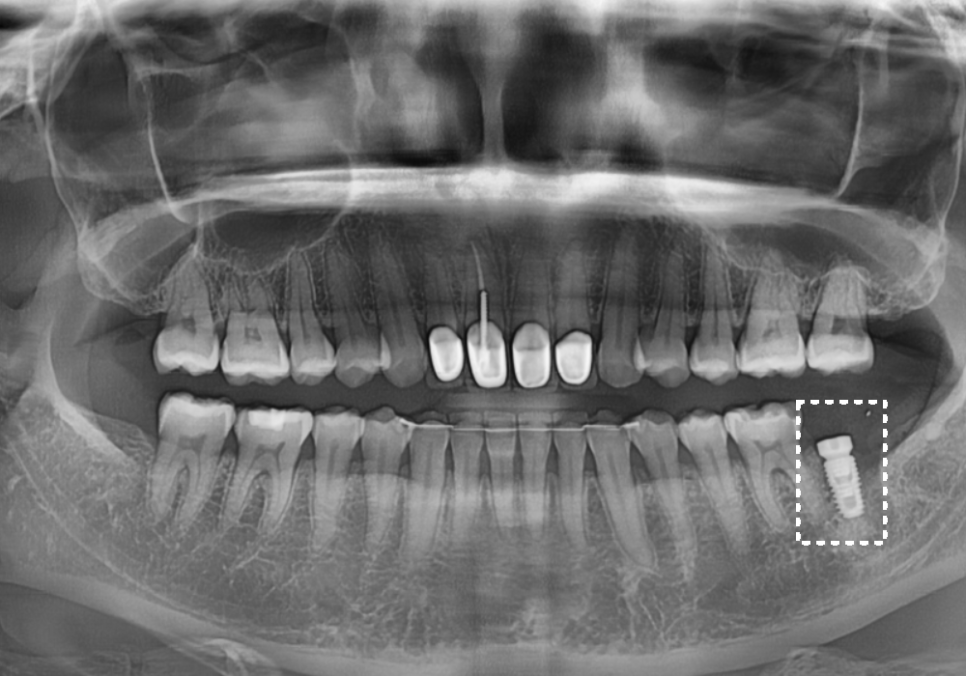

다행히 수술은 아주

안정적으로 잘 마무리되었습니다.

251015

3개월 후, 잇몸 뼈와 임플란트가 하나처럼

단단히 붙은 것을 확인 뒤,

지르코니아로 맞춤 보철물까지

완벽하게 완성해 드렸습니다.^^

2050508(전) 251015(후)